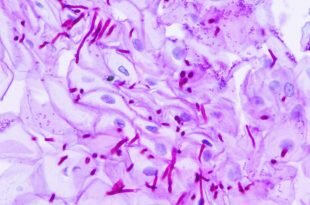

Заболевания печени

Болезни, поражающие печень, несут угрозу всему организму. Причины заболеваний железы — злоупотребление алкоголем или лекарствами, сбои в обменных процессах, инфицирование вирусами, огрехи в питании. Основные болезни — жировая дистрофия железы (гепатоз), воспаления органа различной этиологии (гепатиты), фиброзные и циррозные поражения с замещением паренхимы инертной ткань, дисфункция печени, рак. Клиника болезней скрытая, маскирующаяся под ухудшение общего состояния. Желтуха, боли справа в подреберье, тошнота говорят об усугублении процесса. В основе лечения — строгая диетотерапия, тщательный подбор гепапротекторов, отказ от вредных привычек.